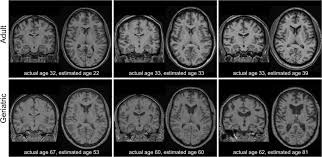

뇌는 그렇게 성실(?)하지 않습니다. 연구들을 종합해 보면 **뇌 노화는 ‘계단식’**으로 진행돼요. 즉, 특정 나이에서 다음 단계로 훌쩍 넘어갑니다.

🧠 뇌 노화의 분기점, 바로 이 나이들

- 40대 중반: 처리 속도·집중력이 서서히 둔해지기 시작

→ “아, 내가 왜 방에 들어왔더라…”가 늘어나는 구간 - 50대 초반: 기억력·멀티태스킹 저하가 체감

→ 이름·단어가 혀끝에서 맴도는 현상 빈번 - 60대 이후: 백질(신경 신호 통로) 변화 가속

→ 학습 속도는 느려져도 경험 기반 판단력은 오히려 강화

왜 ‘계단식’일까?

호르몬 변화, 혈관 탄력 저하, 염증 누적 등이 특정 시점에 겹쳐 나타나면서

뇌의 네트워크 효율이 단계적으로 떨어지기 때문입니다. 매년 1%씩 빠지는 게 아니라, 어느 해에 ‘턱’ 하고 내려가는 느낌이죠.